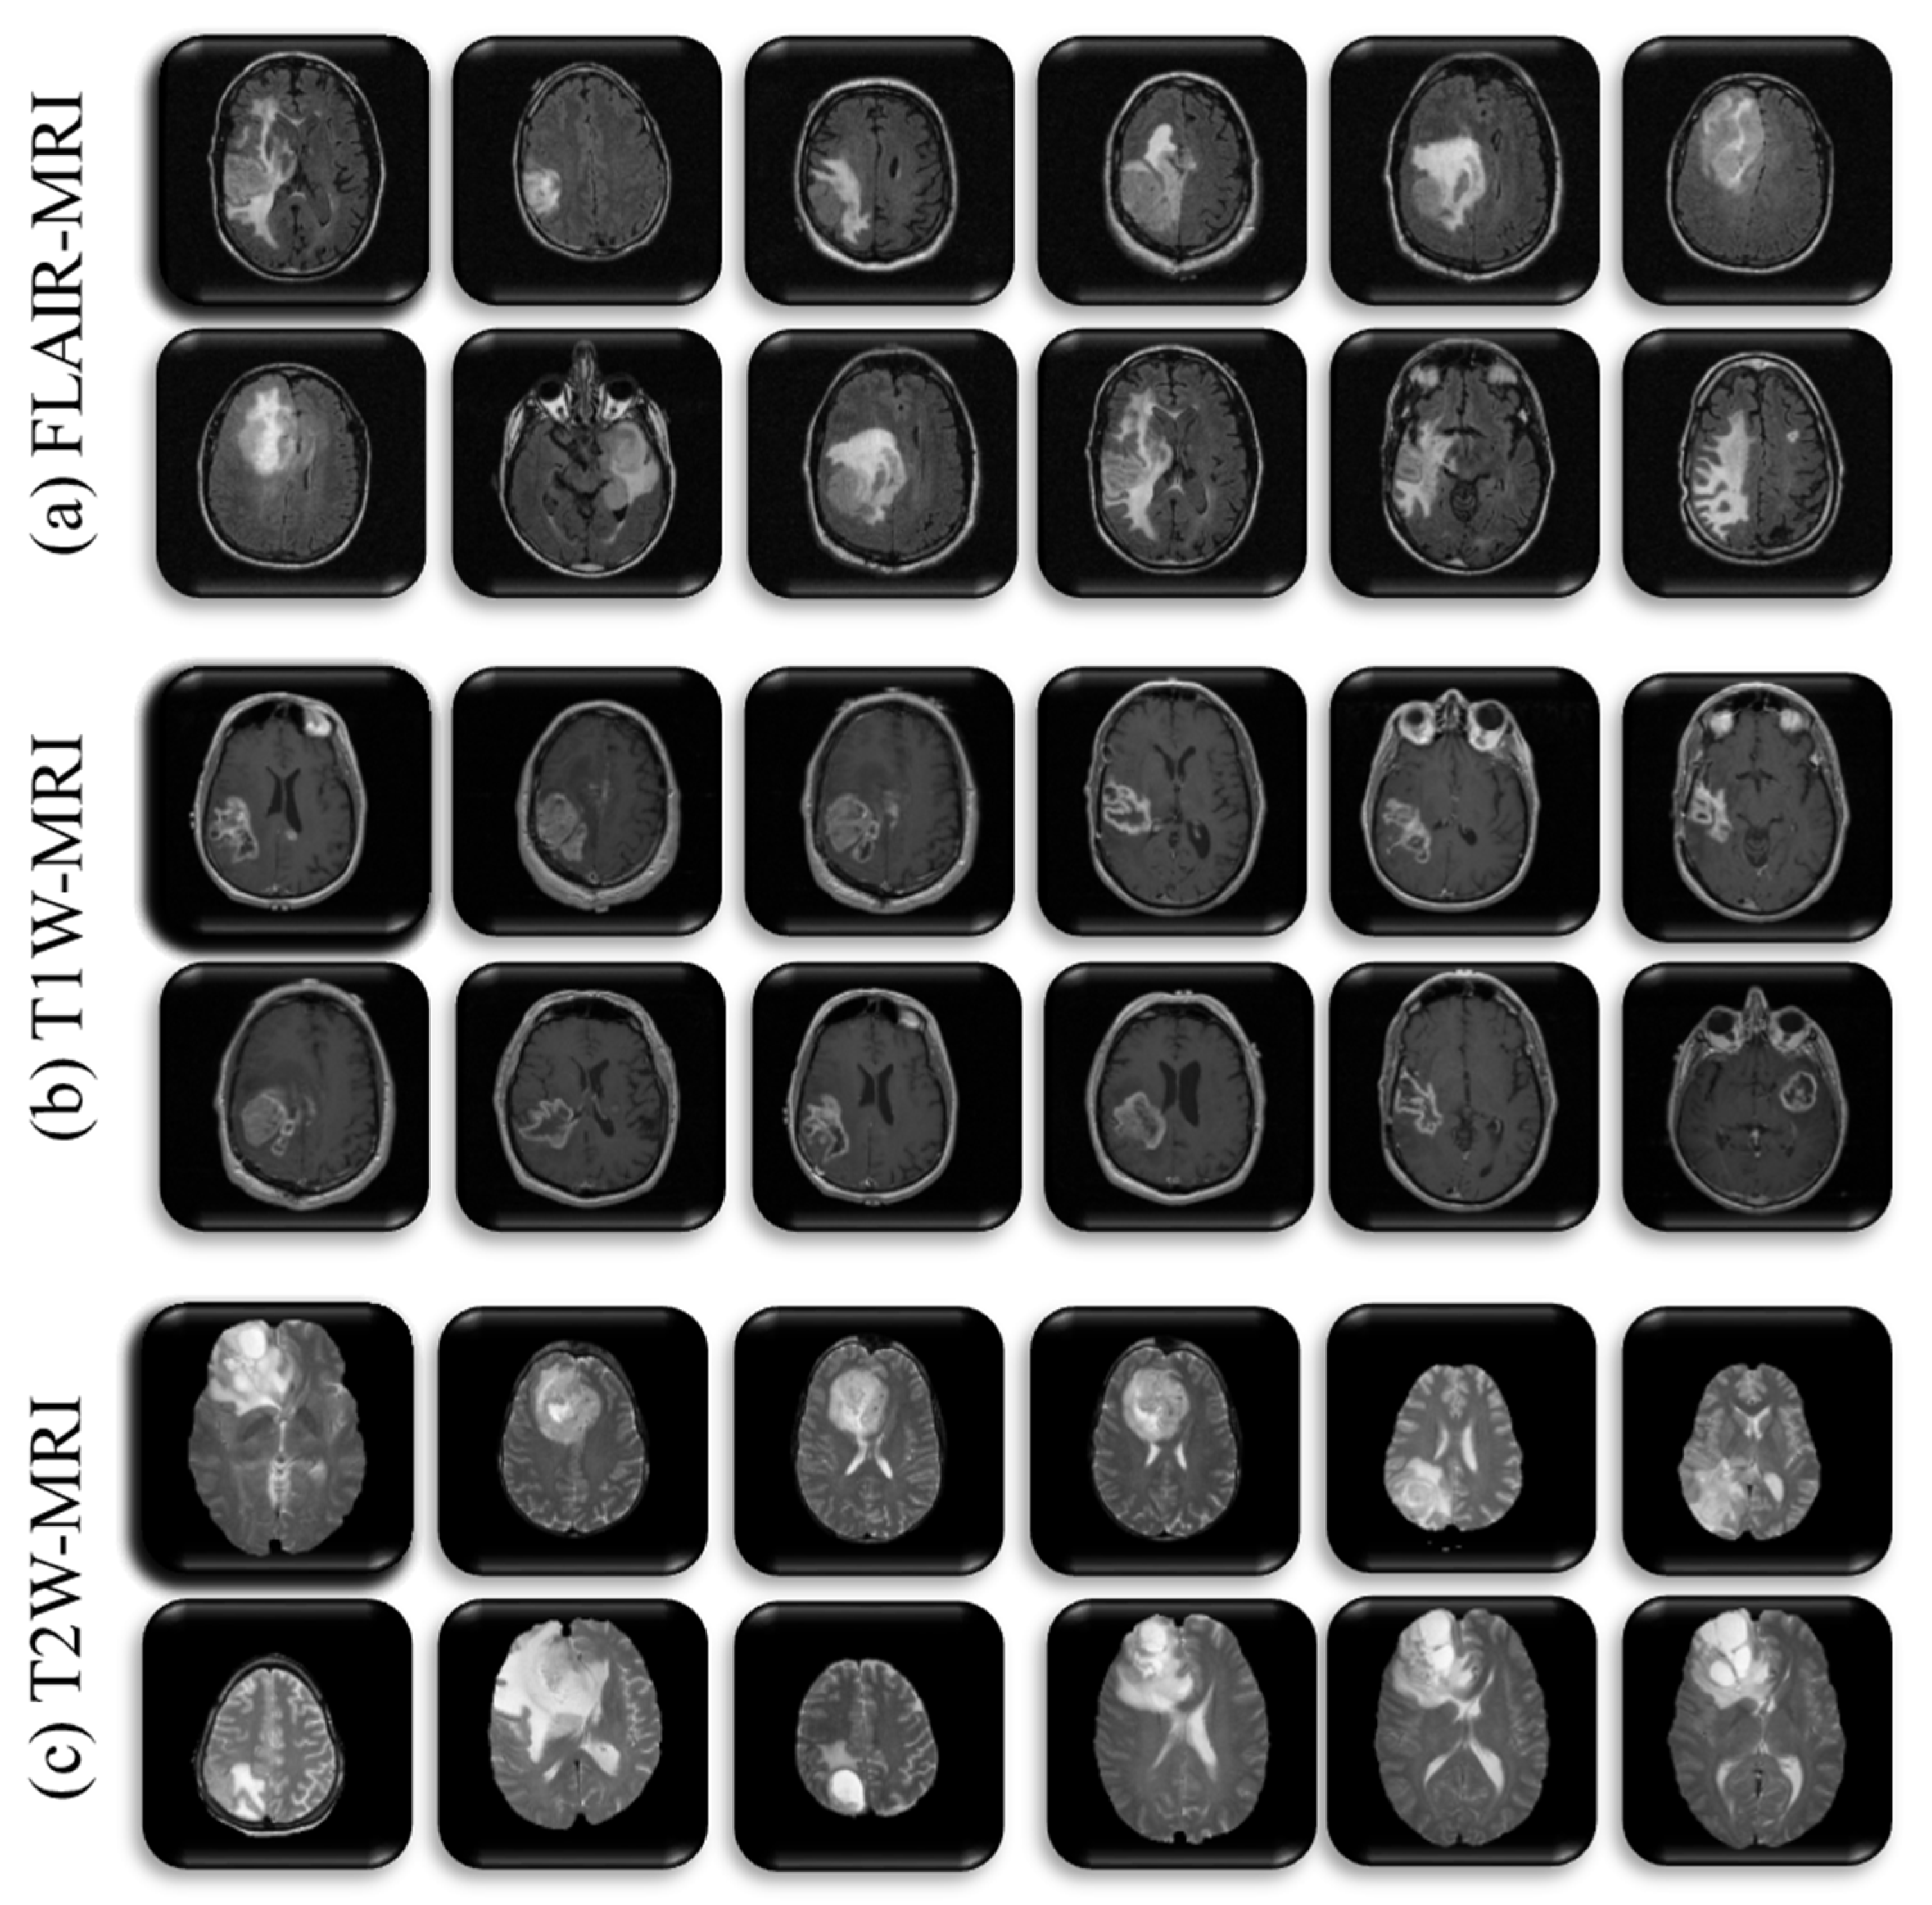

2.1. Data Preparation

3.1.1. T1W-MRI Data Analysis

3.1.2. T2W-MRI Data Analysis

3.1.3. FLAIR-MRI Data Analysis